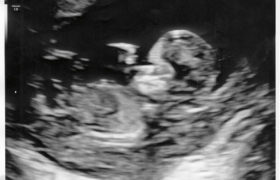

So, a quick recap. 10 Days overdue and knowing we had a chunky baby on the way, we finally found ourselves in a delivery room at the hospital. Labour was pretty intense, and after dealing with unbearably painful contractions brought on by the hormone drip for what felt like an eternity (and that was just how *I* felt!), an epidural was administered, and when it finally kicked in, we both got a little … Read more